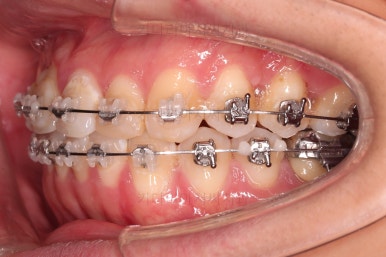

임플란트 완료시 모습인데요.

임플란트 식립부터 완료까지 시간이 걸리다보니 최종 종료까지는 총 19개월이 걸렸습니다.

교합도 잘 맞고 임플란트도 잘 완성되었네요.

매복치아도 손상 없이 잘 배열이 되었고, 교합도 좋게 마무리 되었습니다.